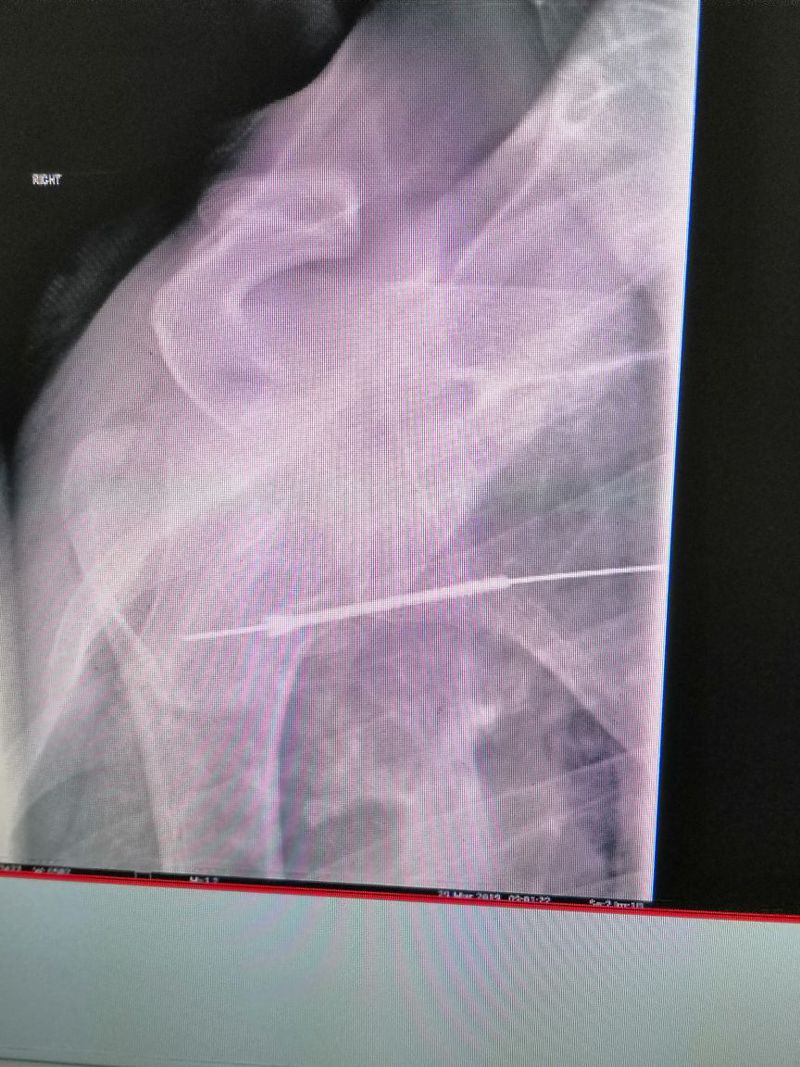

What kind of nail is this?

Shoulder surgery

Surgery

Nail

Shoulder

Skrews